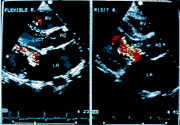

硬质人工二尖瓣环成形术后二尖瓣血流偏向室间隔,而软质人工二尖瓣环成形术后二尖瓣血流不受影响

图3 软质(左图)和硬质(右图)人工二尖瓣环成

形术后彩色血流显像比较

甲组26例软质人工瓣环组术后均为轻微二尖瓣返流。二尖瓣修复术前后心脏各参数的变化见表1。如表所示,二尖瓣环成形术前、后的AM角分别为131.8±6.6度和133.5±8.0度;MI角为88.63±2.38度和87.63±6.23度;左室纵轴与二尖瓣血流柱间夹角均为零度(图3左);二尖瓣平均跨瓣压差为1.95±1.42mmHg和4.21±2.13mmHg;主动脉瓣最大跨瓣压差为3.72±1.79mmHg和6.62±5.90mmHg。各测值术前、后的差别均无显著意义(p>0.05)。

18例行Carpentier硬质瓣环缝置者,术后均为轻微至轻度二尖瓣返流。二尖瓣环成形术后的AM角较术前缩小(术前、后分别为130.7±6.8度和118.0±6.3度)(p<0.01);术前、后MI角的差别无显著意义(分别为93.00±12.47度和89.3±5.7度(p>0.05);与术前相比,术后FI角明显增大(图3右)(分别为零度和22.6±4.2度)(p<0.01);二尖瓣平均跨瓣压差明显增大(1.42±4.7mmHg和5.47±1.7mmHg)(p<0.01),主动脉瓣最大跨瓣压差改变不明显(p>0.05)。